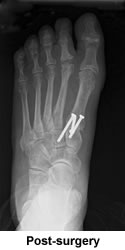

Prior to actually committing myself to the surgery, I contacted Beverly Millar, whose written testimonial was among several on his web site. Thanks to Beverly's helpful advice and reassurance, I finally arrived at one of the most difficult, as well as one of the best, decisions of my life and set the date for surgery. Beverly put me in touch with another of Dr. Leavitt's patients, whose operation was three weeks ahead of mine. Both women, Beverly and Kathy, were familiar with the Roll-A-Bout, an incredible little walker recommended by Dr. Leavitt, without which, convalescence would have been far more difficult. Kathy became my step-by-step guide throughout the process with frequent updates on her progress, preparing me for what to expect next. Nothing was as difficult as I had imagined it would be. With the Roll-A-Bout I was able to zip around the house and eventually up and down the aisles of the supermarket. The ten weeks of disability--which I had dreaded--turned out to be surprisingly comfortable and stress free. The end results were spectacular.

Three months after the second surgery I had the first pedicure of my life, bought my first pair of flip-flops, and headed for Florida. What a thrill to walk on a beach barefoot and pain free! What a joy to lounge by a pool without hiding my feet under a towel! I'm thrilled with my new feet, fused bones, new joints and all. I can now enjoy pilates, long walks, dressy evening affairs, and traversing airport terminals without agony. For once in my life I'm neither ashamed nor embarrassed by my feet. And best of all, I can get through a day without moaning, "My feet are killing me!"

Dr. Leavitt is a perfectionist, totally dedicated to his profession. Contrary to the stereotypical surgeon's lack of bedside manner, he truly cares about his patients, returns phone calls and e-mails, answers all questions, and when he says you'll be able to walk in 10 weeks, you can be sure that you will. For me he was a miracle worker.